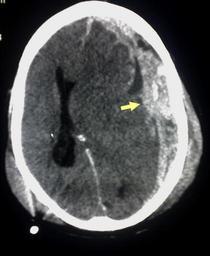

MAKE A MEME View Large Image Trauma subdural arrow.jpg Case images Trauma subdural jpg Trauma subdural arrow jpg Trauma subdural arrows jpg CT snímek subdurálního hematomu with original upload This CT scan is an example of Subdural haemorrhage caused by trauma Arrow ...

Keywords: Trauma subdural arrow.jpg Case images Trauma subdural jpg Trauma subdural arrow jpg Trauma subdural arrows jpg CT snímek subdurálního hematomu with original upload This CT scan is an example of Subdural haemorrhage caused by trauma Arrow added by Delldot <span class signature-talk >talk</span> page is/was http //en wikipedia org/w/index php title Image 3ATrauma_subdural jpg here 2007-06-24 Modified 04 23 2 November 2008 UTC Glitzy queen00 wikipedia en 100px Glitzy queen00 original upload log All user names refer to en wikipedia 2007-06-24 17 16 Glitzy queen00 1159×1415×8 243496 bytes <nowiki>This CT scan is an example of Subdural haemorrhage caused by trauma </nowiki> Subdural hematoma Computed tomography images of the brain CT images of brain herniation